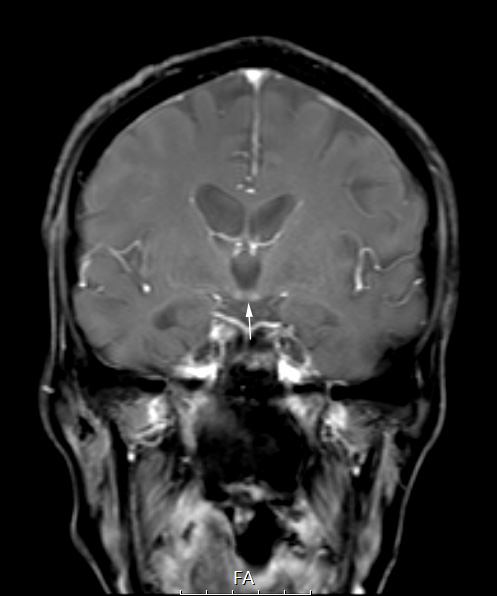

18A1 (Case18) Wernicke FL2D T1 FS POST contrast copy

This T1-weighted post contrast scan shows slight but compelling hyperintensity and enhancement.